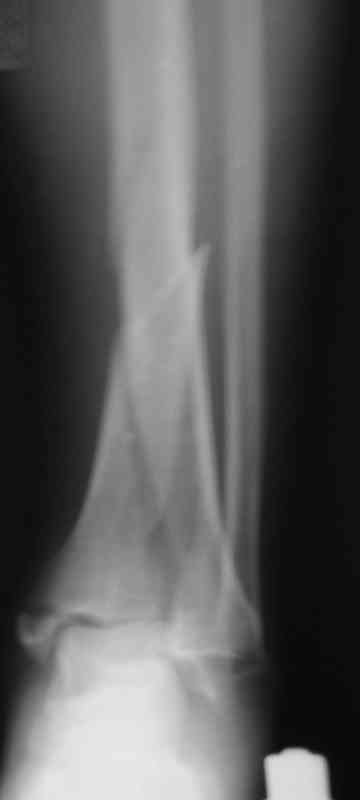

Мы бы фиксировали пластиной м/берцовую кость открыто, на б/берцовую пластину MIPO, при необходимости сустав открыть минимально.

На фото простой суставной, метафиз. оскольчатый с переходом на диафиз перелом, пластина MIPO.

С Уважением А.Миронов

Андрей Миронов показал более симпатичную картинку.

Коллеги подсказали различные варианты фиксации, включая минимальный открытый метод с фиксацией в аппарате Илизарова (Артемьев), а также перкутанный метод (Миронов) пластиной с угловой стабильностью.

Несмотря на различия методик, оба случаи, кстати сделанные на превосходном уровне, заслуживают внимания тем, что первостепенной задачей был поставлено восстановление суставной поверхности.

После восстановления сустава, не думаю, что были бы какие-то сложности в репозиции крупнооскольчатых переломов голени с применением минимально-открытой или закрытой методик.